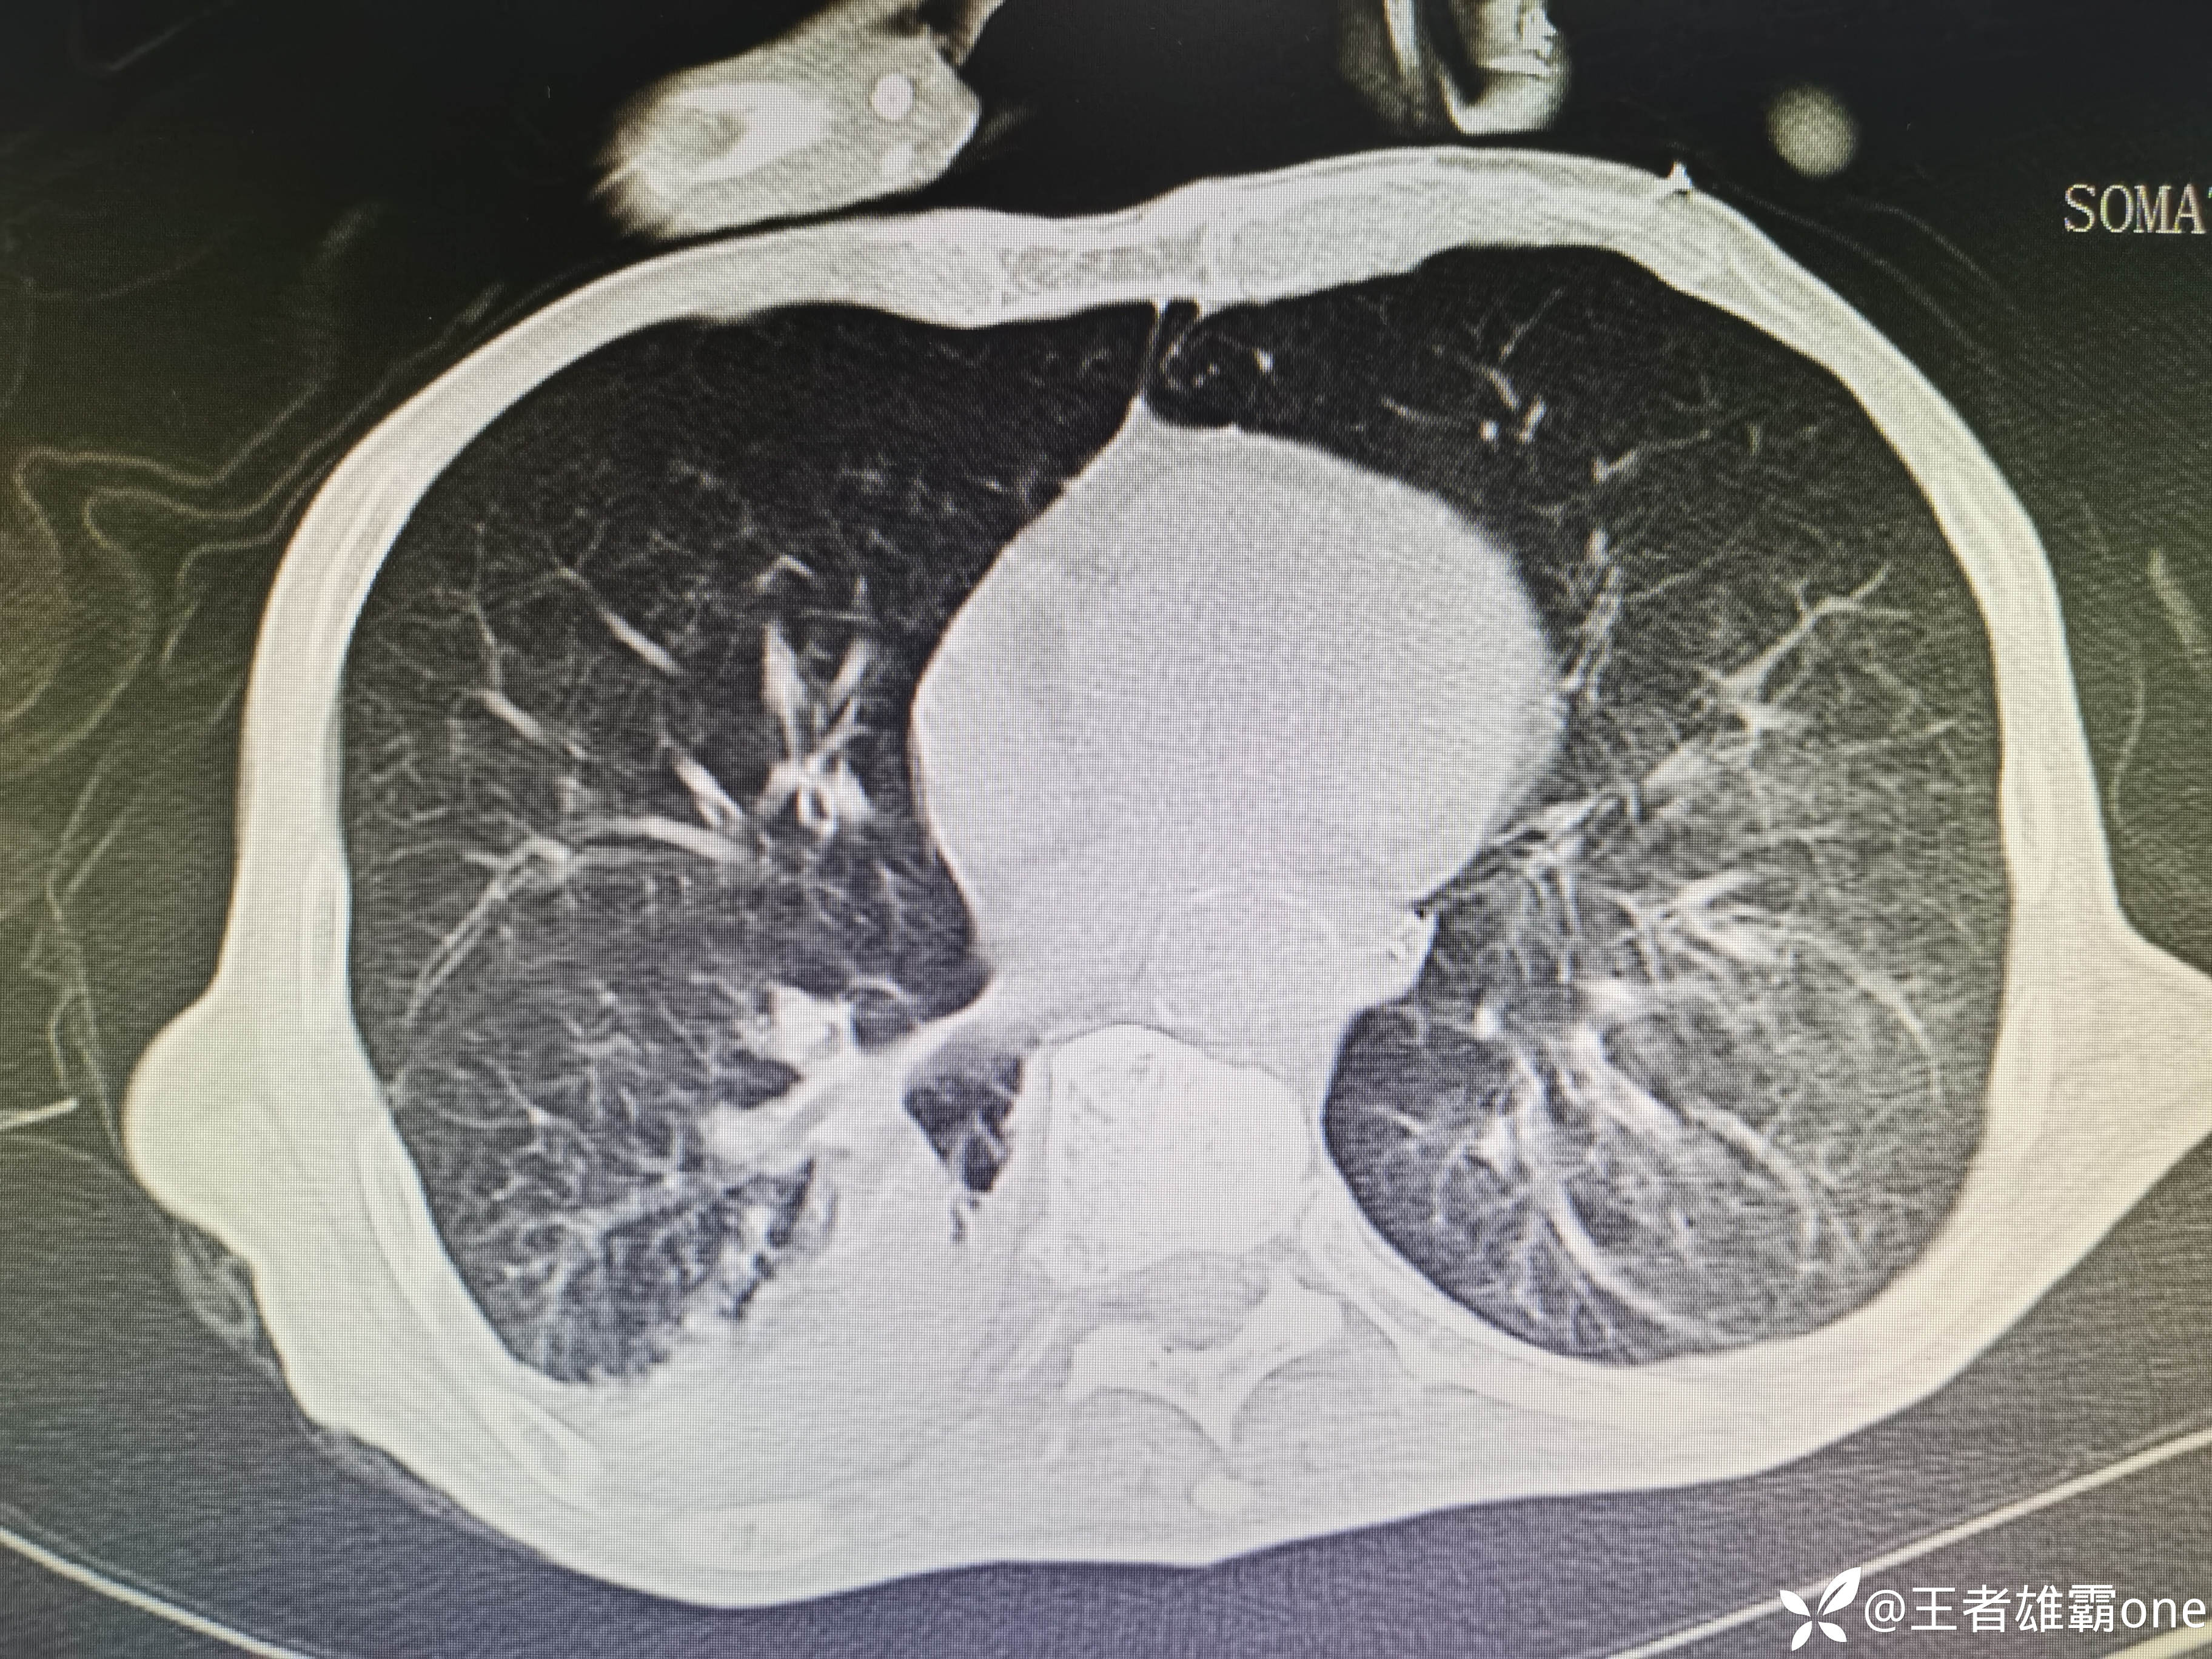

入院时胸部CT:

具体图片: